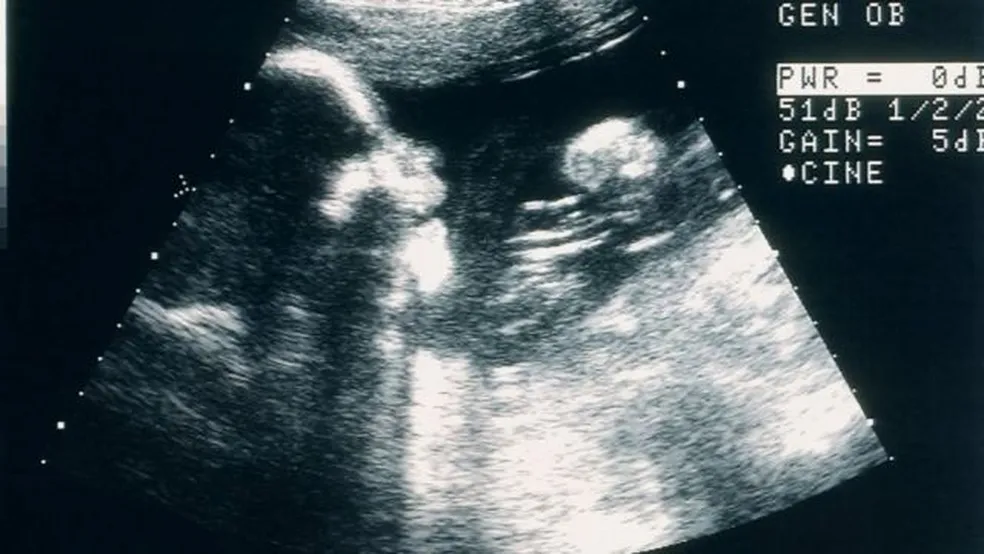

No dia 9 de novembro de 2022, ela deu à luz Machó e Lylah, ambos pesando 2 libras e 8 ounces [cerca de 1.100 kg], e Trinity, que nasceu pesando 2 libras e 1 ounces [cerca de 935 gramas], tudo por meio de cesariana. Os três bebês passaram 50 dias na UTI para ganhar peso e, agora, com seis meses, estão em casa. Monique, que é diretora-assistente de educação, compartilhou: “Quando os médicos me disseram que eu não poderia ter filhos, foi devastador. Mas, quando o ultrassonografista disse que eram trigêmeos, eu apenas gritei de confusão e felicidade. Acabei chorando em cima da mesa. Tem sido uma bênção com tantos desafios. Os médicos os chamavam de bebês milagrosos.”